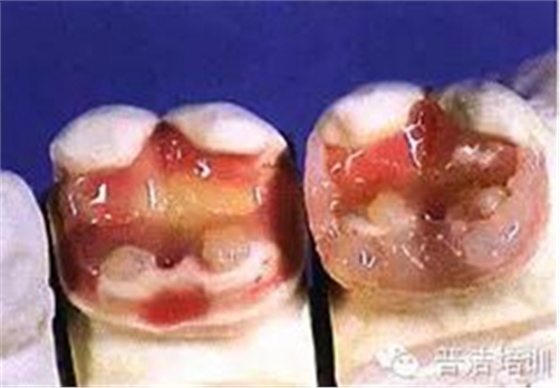

十、試戴樹脂高嵌體

十一、分開粘結(jié),用聚四氟乙烯保護(hù)修復(fù)好的牙齒

十二、洞內(nèi)置入粘結(jié)水門汀,將高嵌體就位

十三、用器械使修復(fù)體完全就位

十四、完全就位前去除多余的水門汀,并用牙線和探針仔細(xì)去除牙齒之間的多余材料。

十五、修正、拋光

十六、最終的修復(fù)體,是不是很漂亮